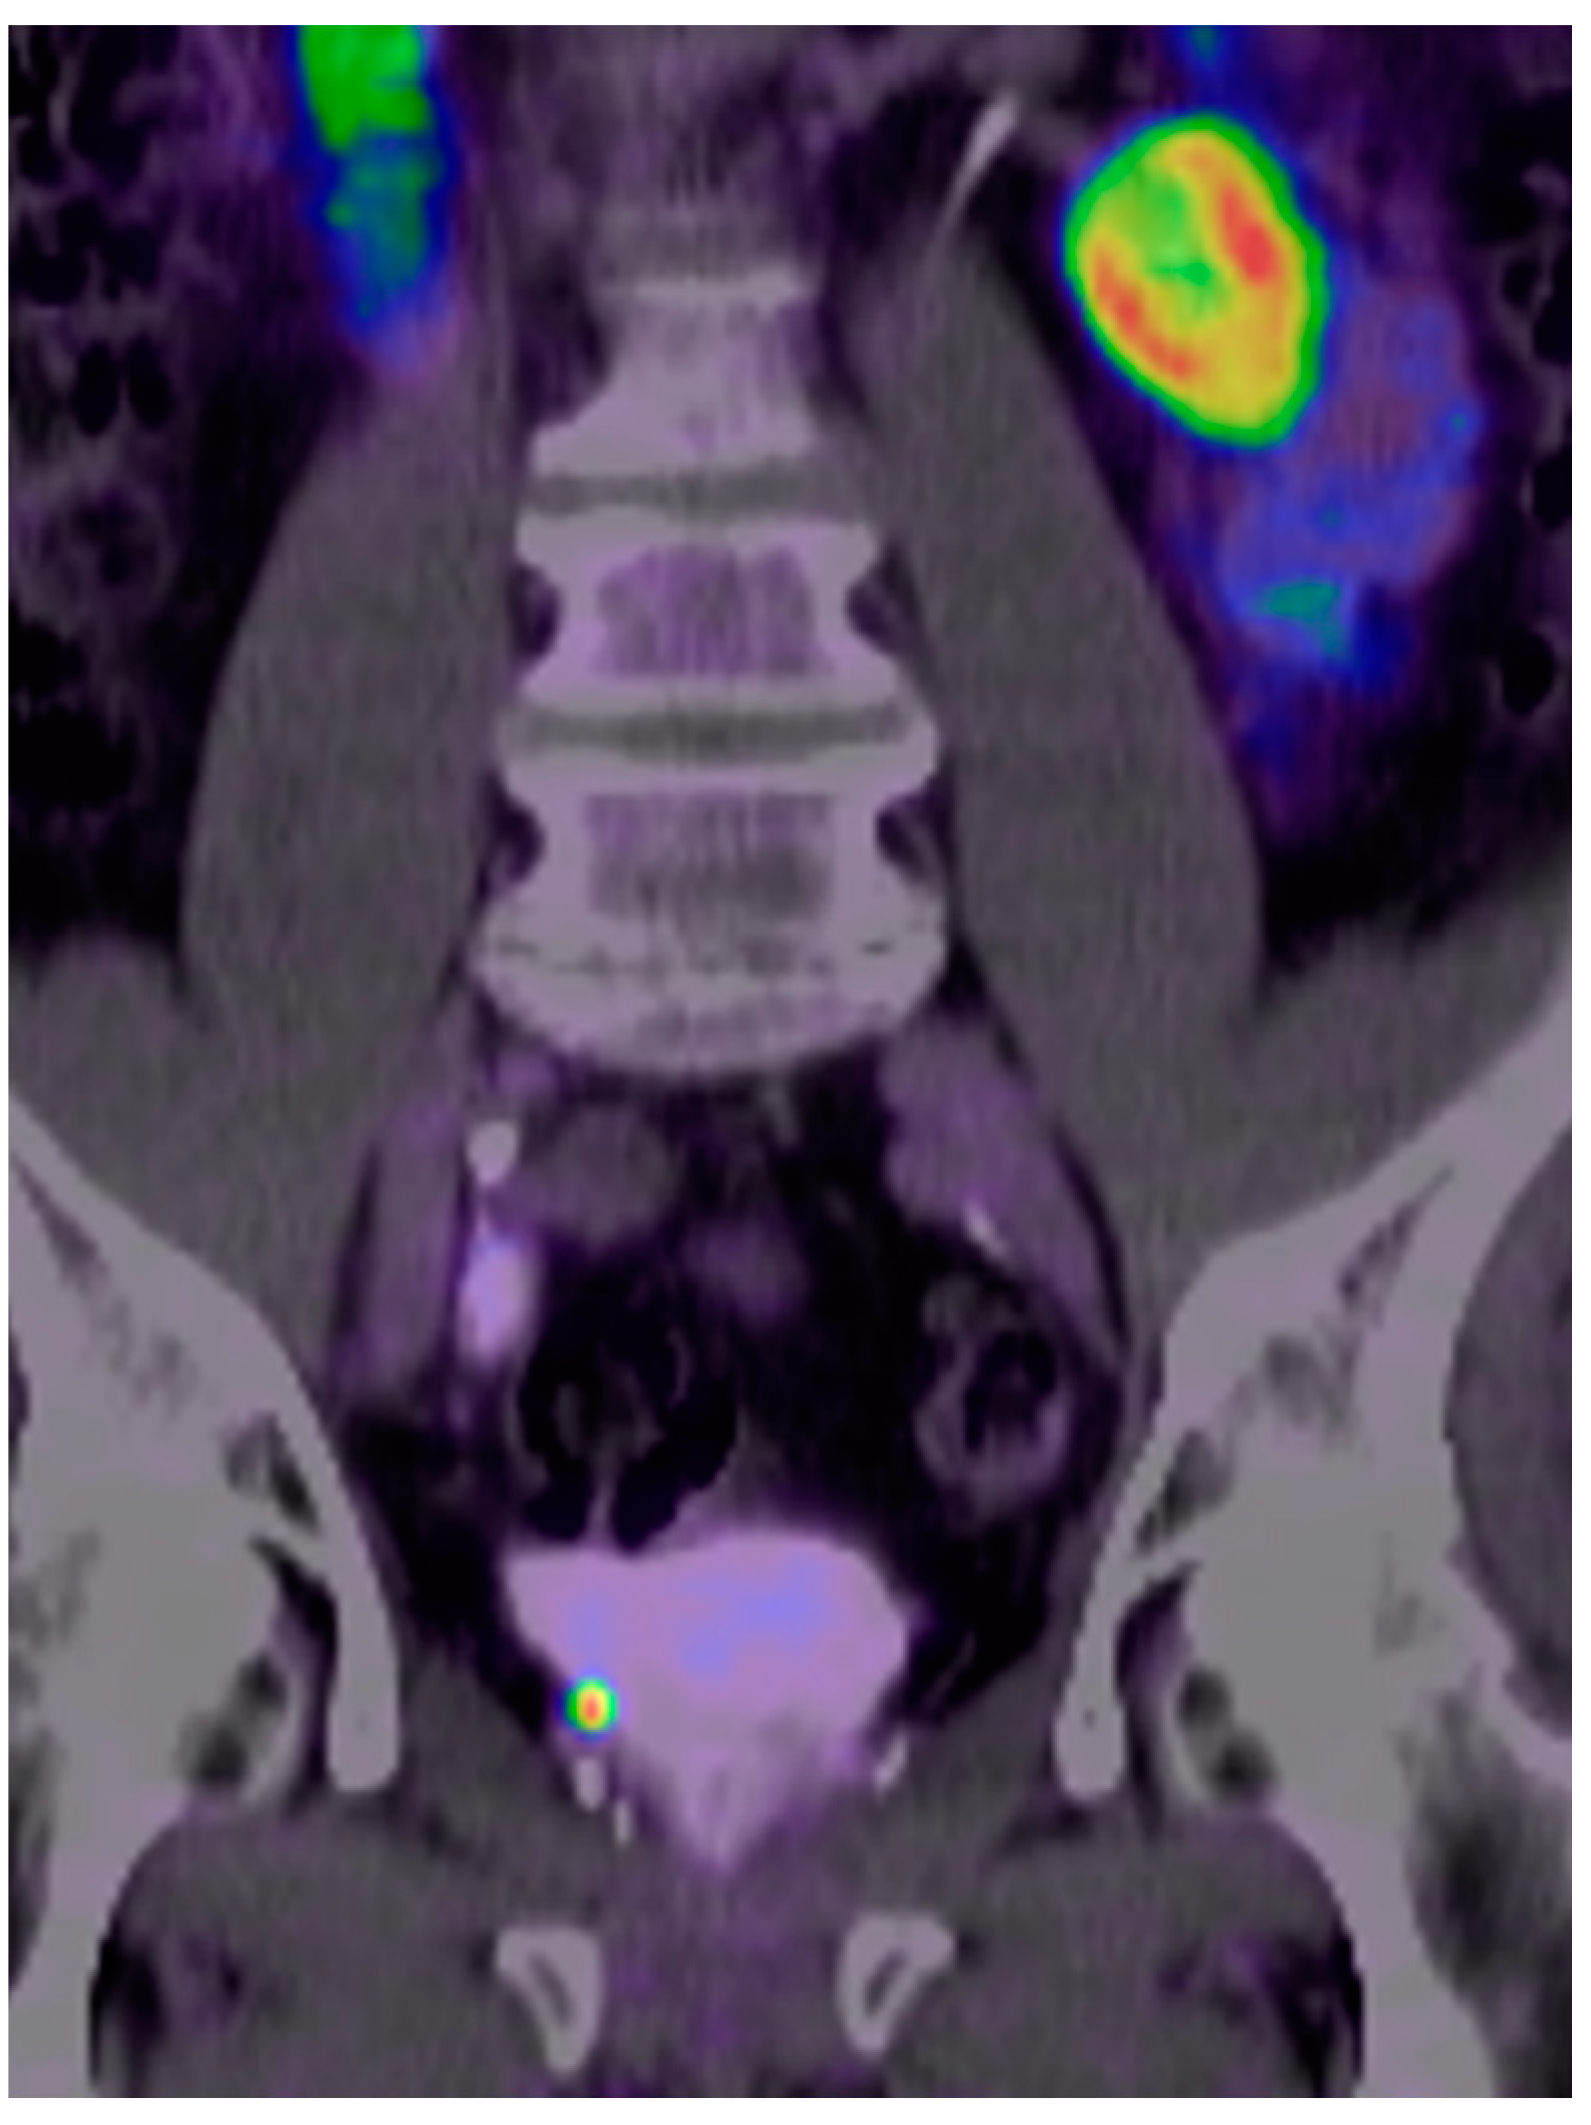

Comparison of [18F]PSMA-1007 with [68Ga]Ga-PSMA-11 PET/CT in Restaging of Prostate Cancer Patients with PSA Relapse

2.2. Imaging Protocol and Analysis